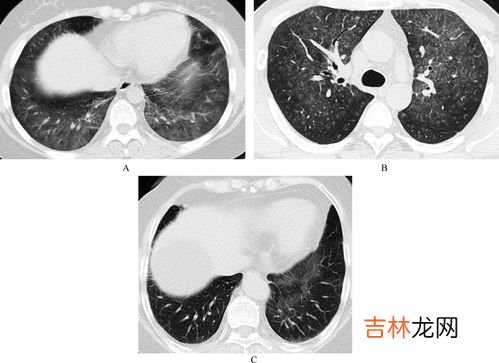

文章插图

间质性肺炎间质性肺病是以弥漫性肺实质、肺泡炎和间质纤维化为病理基本改变,以活动性呼吸困难、X线胸片示弥漫阴影、限制性通气障碍、弥散功能降低和低氧血症为临床表现的不同类疾病群构成的临床病理实体的总称 。

间质性肺疾病(ILD)是以弥漫性肺实质、肺泡炎症和间质纤维化为病理基本病变,以活动性呼吸困难、X线胸片弥漫性浸润阴影、限制性通气障碍、弥散(DLCO)功能降低和低氧血症为临床表现的不同种类疾病群构成的临床-病理实体的总称 。

间质性肺炎是以肺泡壁为主要病变所引起的一组疾病群,是以弥漫性肺实质、肺泡炎和间质纤维化为病理基本改变的 。